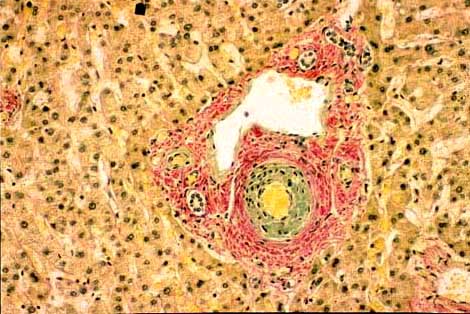

10-1-2.jpg (41037 bytes)

Fig. 10-1-2: Eclampsia.

Focal hemorrhagic infarct with epatocellular necrosis. These small infarcts are mostly located in periportal areas. Notice the extensive necrosis in the right side of the picture.H&E stain

10-1-3.jpg (30858 bytes)

Fig.10-1-3: Eclampsia.

Periportal area with hepatocellular necrosis and fibrin thrombi in the sisusoids. Masson stain.

Multiple small hemorrhagic infarcts are the characteristic of toxemia of pregnancy consisting of Pre-eclampsia and Eclampsia mostly occurring in late, third trimester of pregnancy.

Pre-eclampsia consists of hypertension, proteinuria and edema. The addition of convulsions characterizes eclampsia. These conditions are systemic with leukocytosis, hemolytic anemia, thrombocytopenia and disseminated intravascular coagulation (DIC). The liver is secondarily involved. Jaundice is rare and mild. Histologically the liver may shows non-specific portal inflammation, periportal canalicular cholestasis, diffuse sinusoidal dilatation, focal ballooning of hepatocytes and presence of eosinophilic bodies. Multiple small hemorrhagic infarcts and necrosis are seen in15-20% of the cases.

The hemorrhagic infarcts are due to fibrin thrombi in small portal veins and in periportal sinusoid. Periportal fibrin thrombi have been observed even in normal pregnancy. (Rolfes DB &Ishak AG: Am. J. Gastroenter.81:1138, 1986) Thrombosis of a hepatic artery caused by DIC will result in ischemic infarcts of the liver. These changes subsidize promptly after delivery but if there is the combination of hemolysis (H), elevated liver enzymes (EL) and low platelets (LP), the fatidic HELLP syndrome there will be 10% infant mortality and 3-4% maternal mortality.